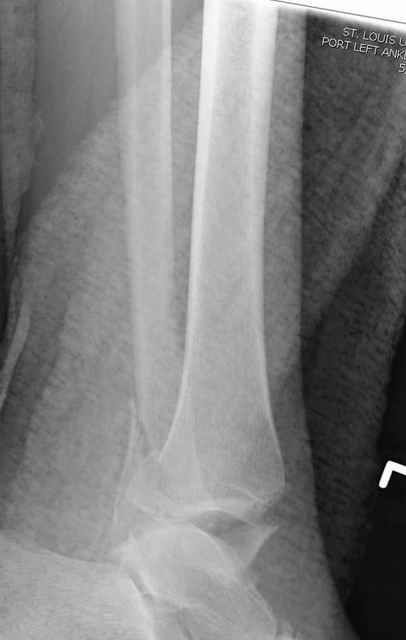

Re: ANKLE FRACTURE

Alexander Chelnokov 12 Сентябрь 2004, 15:11

Я вот все в толк не возьму смысл отдельной фиксации малоберцовой кости пластинкой, если все равно будет аппарат с фиксацией стопы, т.е. возможностью провести спицы в пятку, таран, наружную лодыжку и еще черт-те куда. Остеосинтез пластинкой выглядит логичным в случае, когда наружная фиксация планируется как временная. Но тут-то аппарат будет окончательным фиксатором.

Еще, кстати, о фиксации лодыжки, если уж непременно хочется ее отдельно стабилизировать - при таком характере перелома замечательно должен сработать предложенный проф. Лазаревым с соратниками способ фиксации напряженной V-образной спицей. Опять же, открытая репозиция не нужна, мы делаем непрямую репозицию именно аппаратом. В приложении пример, там перелом малоберцовой куда менее поперечный, чем в данном случае, но все равно получилось закрыто без пластинки.

I can't realize why plate fibula separately if anyway external fixator including the foot is planned, i.e. one may insert wires to the talus, calcaneus, lateral malleolus and anywhere else. Plating looks reasonable if only temporary ex-fix is planned, but in the case it will be definitive.

A propos fibular fixation if one is eager to stabilize it separately. In the fracture pattern a way of closed fixation by V-shaped stressed wire (advanced by colleagues from Moscow, prof. Lazarev A.F. et al.) must be excellent. We use indirect closed reduction by the external fixator. Example attached, that fibular fracture is even more suitable for plating but the wire did the job.